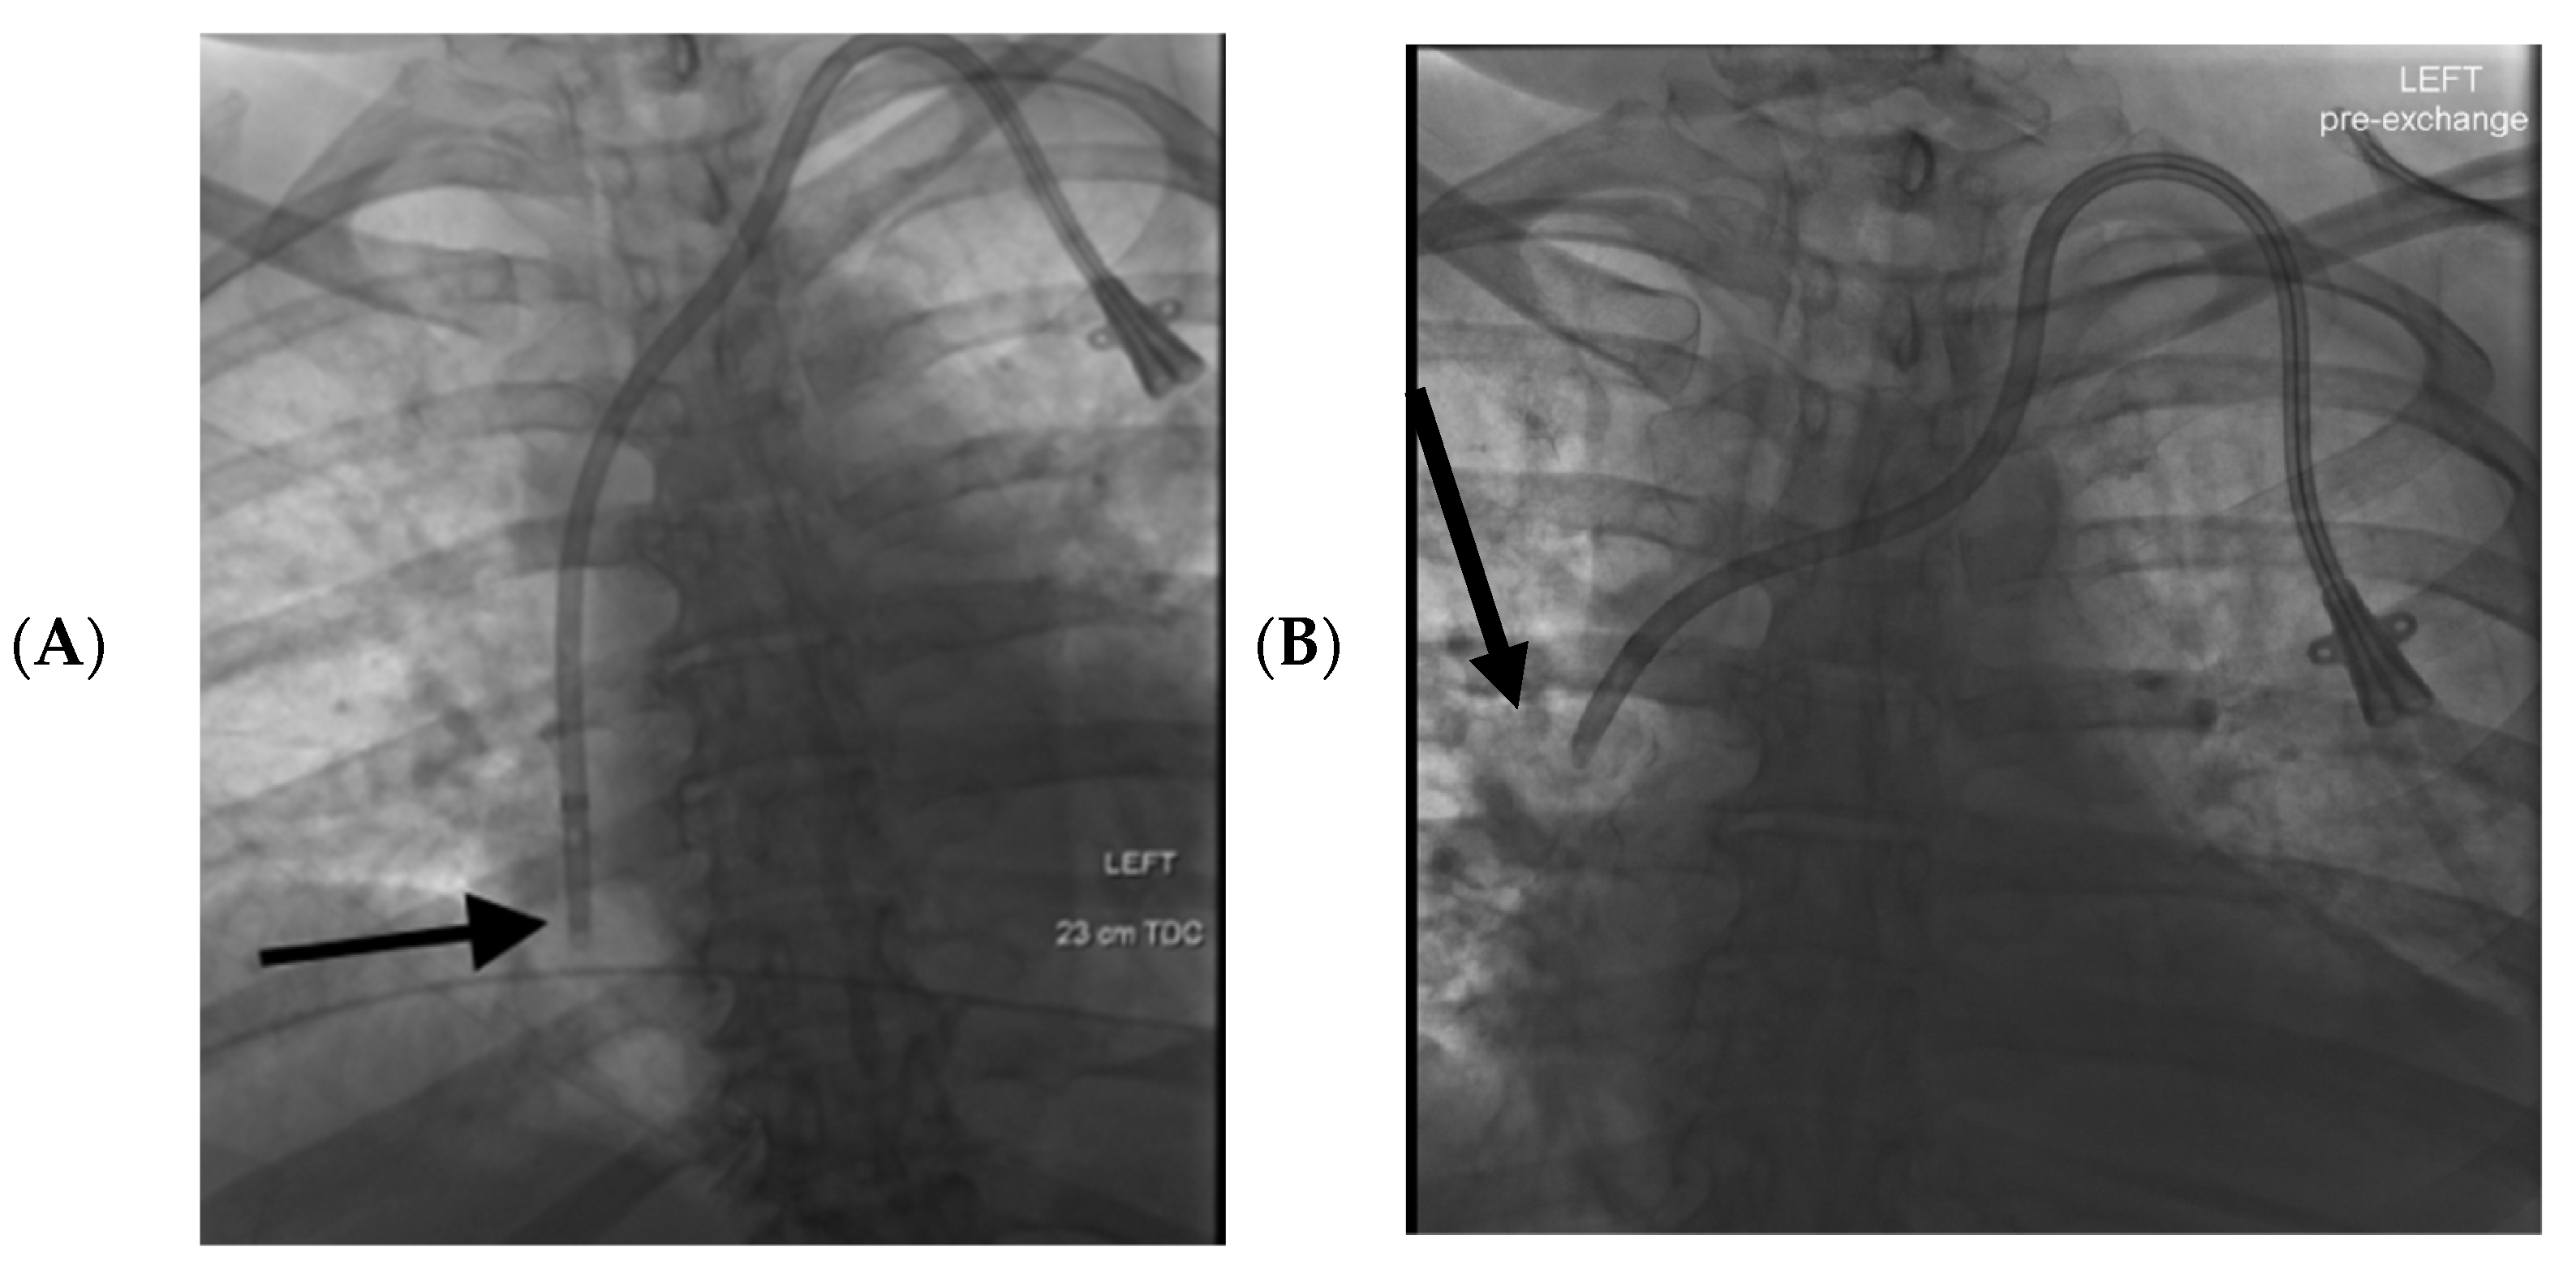

(A) Hemodialysis catheter tip malposition induced catheter mal func Dialysis Catheter Tip In Right Atrium The right atrium is preferred over the superior vena cava (svc) for tunnelled dialysis catheter (tdc) tip placement as it offers the. Choosing the correct catheter tip will allow good positioning and draw of approximately 400 ml/min. Normal right atrium the normal right atrium consists of a large right atrium that will accommodate many different types of cath. When the. Dialysis Catheter Tip In Right Atrium.

Malfunction of Dialysis Catheters Management of Fibrin Sheath and Dialysis Catheter Tip In Right Atrium When the abdominal organs descend, the mediastinal structures (including the central veins and the right atrium) lengthen, causing the catheter tip to be at a higher. For catheters placed through the internal jugular vein or subclavian vein, the optimal tip location is at the junction of the superior vena cava and right atrium, and catheters. Place the catheter so that. Dialysis Catheter Tip In Right Atrium.

Fluoroscopic image of chest showing the 28 cm tunnelled dialysis Dialysis Catheter Tip In Right Atrium When the abdominal organs descend, the mediastinal structures (including the central veins and the right atrium) lengthen, causing the catheter tip to be at a higher. Choosing the correct catheter tip will allow good positioning and draw of approximately 400 ml/min. One major challenge when inserting a tunneled, cuffed central venous catheter (cvc) for hemodialysis under fluoroscopy is to. Applying. Dialysis Catheter Tip In Right Atrium.